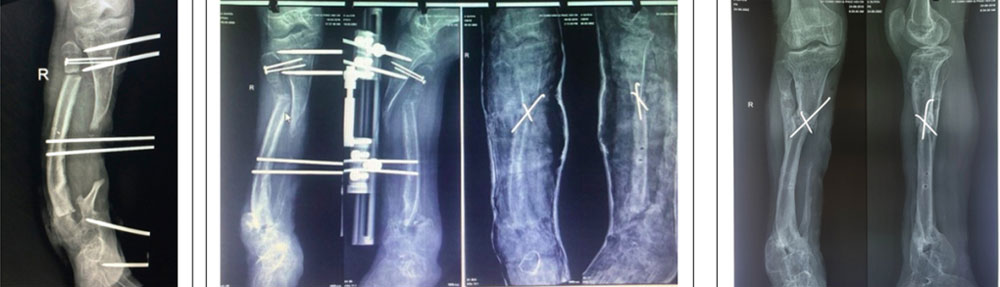

Hình ảnh X Quang về diễn tiến trong quá trình phẫu thuật của bệnh nhân. Ảnh: Bệnh viện cung cấp |

Suyên được mổ cắt xương mác hai đầu, đặt khung cố định ngoài kéo giãn ổ khớp giả để kéo dài cẳng chân. Sau một tháng, ổ kéo giãn tăng thêm 8,3 cm, chàng trai bước vào cuộc phẫu thuật lần hai.

Hai cuộc mổ thành công cùng với nghị lực tập phục hồi chức năng đã giúp ổ khớp giả kéo giãn 15 cm, sau 4 tháng. Các bác sĩ quyết định phẫu thuật chuyển đầu gần xương mác vào đầu gần ổ khớp giả xương chày. Sau mổ, bệnh nhân được thiết kế mang nẹp chỉnh hình riêng và tập phục hồi chức năng.